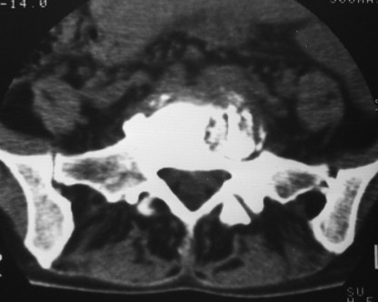

以下是引用dyqct在2007-3-1 18:04:00的发言:[br]腰5、骶1呈溶冰状骨质破坏,边界清楚,无明显硬化,内见多数沙粒状死骨,周围软组织肿胀。[br]考虑:腰5、骶1结核,建议严格抗结核治疗后复查。

以下是引用gaoxiao在2007-3-1 18:02:00的发言:[br]腰5骶1椎体见骨质破坏,其内见死骨形成,椎前软组织肿胀,感染性病变,腰骶椎tb。

以下是引用gaozhengyi在2007-3-1 19:39:00的发言:[br]骨质破坏并砂砾样死骨为椎体结核的表现。椎体结核骨质破坏区的特点是呈虫蚀状,常可见硬化缘。死骨表现为片状高密度影,正如本例。